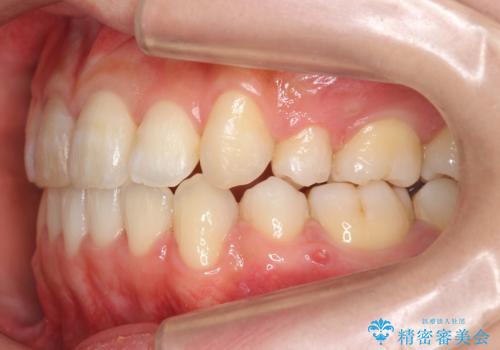

- 前歯のがたがたを主訴に来院。

八重歯と、前歯のやや開咬の症状もあり難易度としては中等度でした。

上下左右の小臼歯を抜歯し、ワイヤー矯正を行いました。

右上の前歯は変色もあり、神経の治療後にセラミックを被せる予定です。